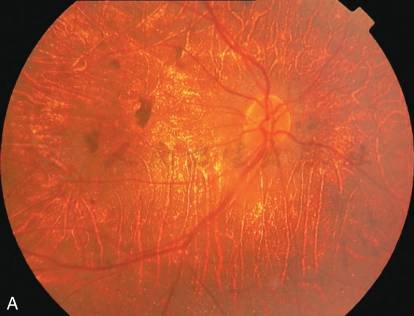

图1弥漫性脉络膜视网膜萎缩

A和B.双眼脉络膜视网膜萎缩,露出脉络膜大血管,呈黄色或白色;C和D.双眼OCT证实视网膜外层、RPE层和脉络膜全层萎缩